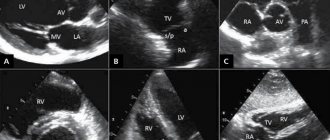

Для правильной диагностики в акушерской практике применяют трехмерное ультразвуковое изображения. При помощи этого современного диагностического метода появилась перспектива диагностировать ретроплацентарное кровотечение, оценивать пороки развития сердца с помощью наблюдения за током крови. Метод незаменим, так как помагает увидеть девекты даже в наименьших сосудах.

Оценка кровотоков в артерии пуповины на фоне СЗРП

Допплеровское исследование скорости тока крови в АП является в настоящее время обязательным условием диагностики и степени тяжести СЗРП [12]. В ранних исследованиях [13], проведенных на эмбрионах цыпленка и экспериментальных животных, было показано, что эмболизация стеклянными микросферами сосудов котиледона по ходу АП сопровождается повышением сосудистого сопротивления и увеличением систолодиастолического отношения скоростей тока крови (S/D) в А.П. По мере развития плаценты в ходе нормальной беременности происходит уменьшение ее сосудистого сопротивления и уменьшение S/D [14—16]. В случае СЗРП по мере увеличения гестационного срока снижение S/D значительно меньше [17]. Морфологические исследования плацент показали тесную корреляцию микроскопических изменений сосудов ворсин плаценты и гемодинамических показателей при СЗРП [18—21].